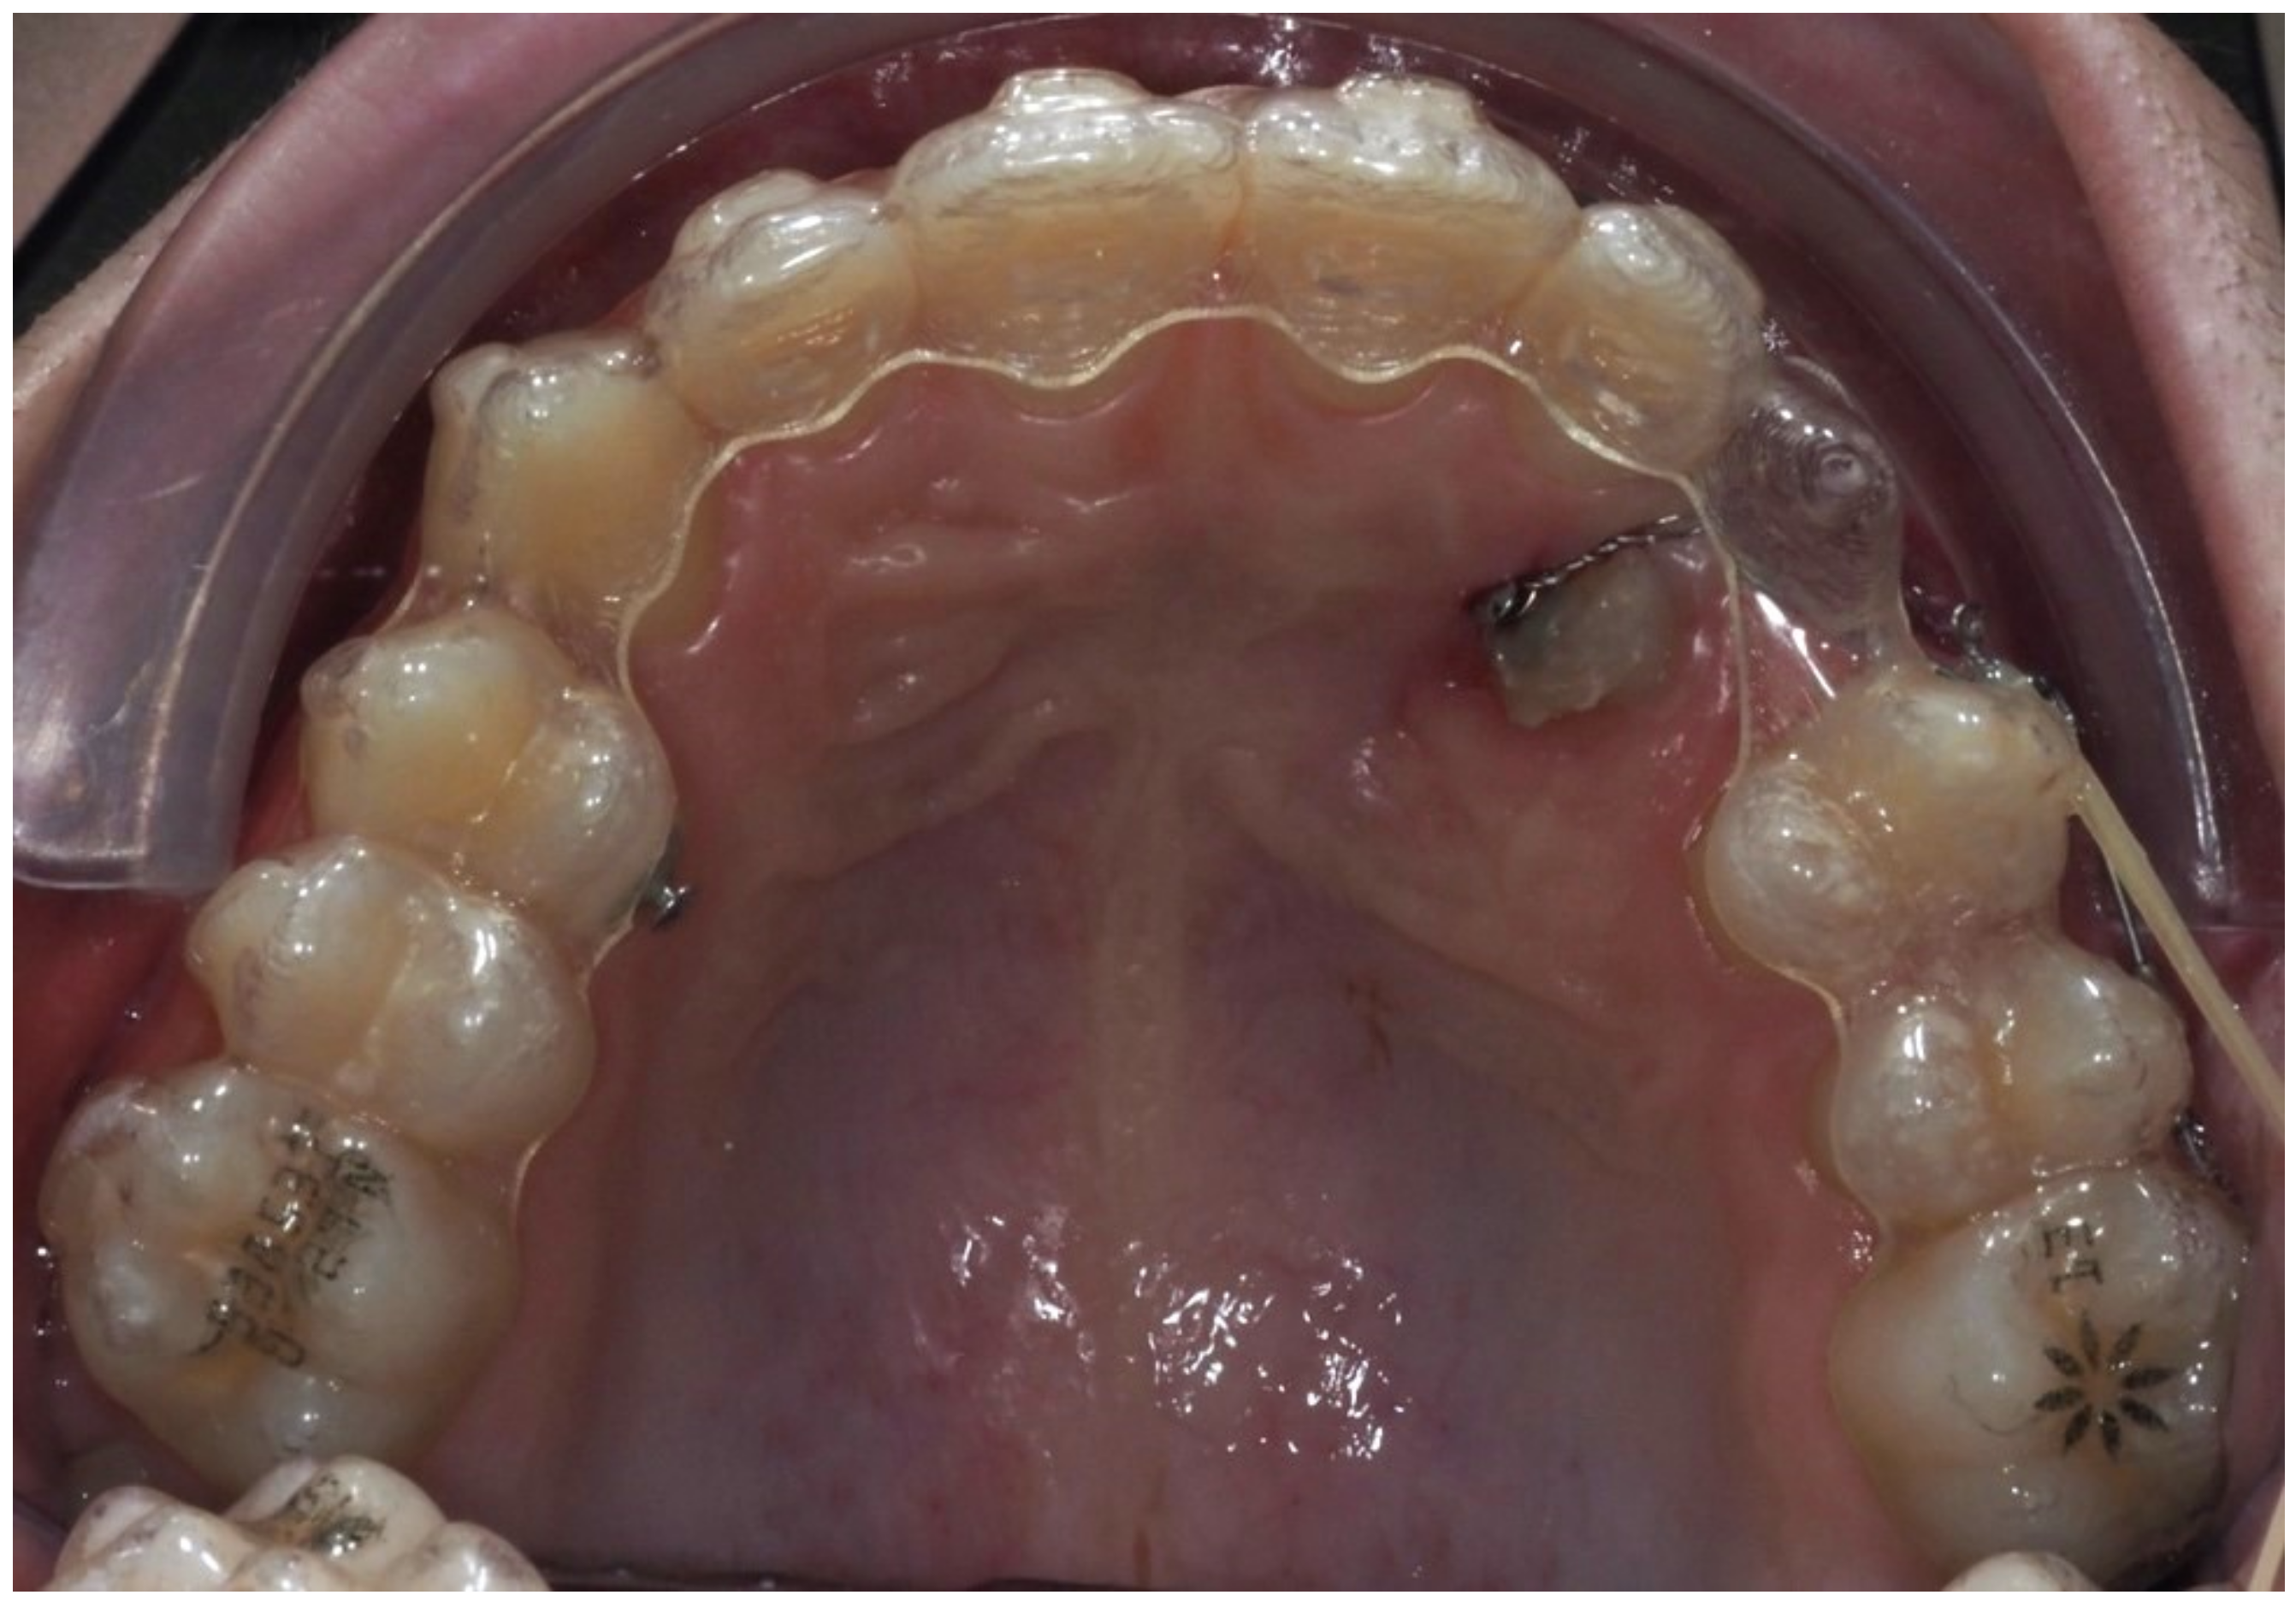

As traction progressed, the sectional appliance was extended to tooth 21 (Figure 19). A palatal button was bonded on tooth 23 to facilitate cross elastic application for vestibular movement (Figure 20). At 20 months, the bracket on tooth 23 was progressively repositioned more cervically and mesially to aid extrusion and derotation (Figure 21). A button was bonded on tooth 22 to support a wire for additional vertical anchorage. Cross elastics were also used between the palatal side of tooth 23 and buttons on teeth 33 and 34, while another elastic connected tooth 22 to 33 (Figure 22).

Figure 20.

Palatal button on tooth 23 for cross elastic to assist in its vestibularization; 18 months of treatment.